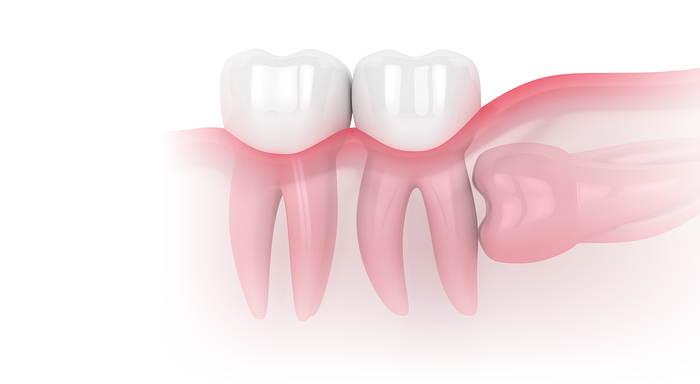

사랑니는 우리 입속에 가장 뒤에 난 어금니를 말하며, 전문용어로 설명해 드리면 제3대구치라고 하며 얼굴을 중심으로 좌우로 8번째 자리하고 있는 치아를 말합니다. 사랑니는 사춘기 이후에 자란다고 합니다. 사춘기에는 여러 가지 감정을 느끼게 되고 그 감정 중 하나가 사랑이라는 감정이지요. 그래서 이 치아를 사랑니라고 부른다고 합니다.

치과 치료를 하면 알 수 있는 것이 치아는 함부로 뽑지 않습니다. 정말 최대한 살려보고 그래도 안 되면 뽑아서 임플란트 등으로 빈자리를 채웁니다. 사랑니는 다른 치아들과 달리 발치를 해야 할 때도 있습니다. 잘 자란 사랑니는 특별한 문제를 일으키지 않아 뽑지 않아도 됩니다. 하지만 대부분의 사랑니는 말썽을 부립니다. 출혈, 염증, 통증 및 악취, 충치 들 여러 가지 문제를 일으킬 확률이 높기 때문에 뽑아야 합니다.